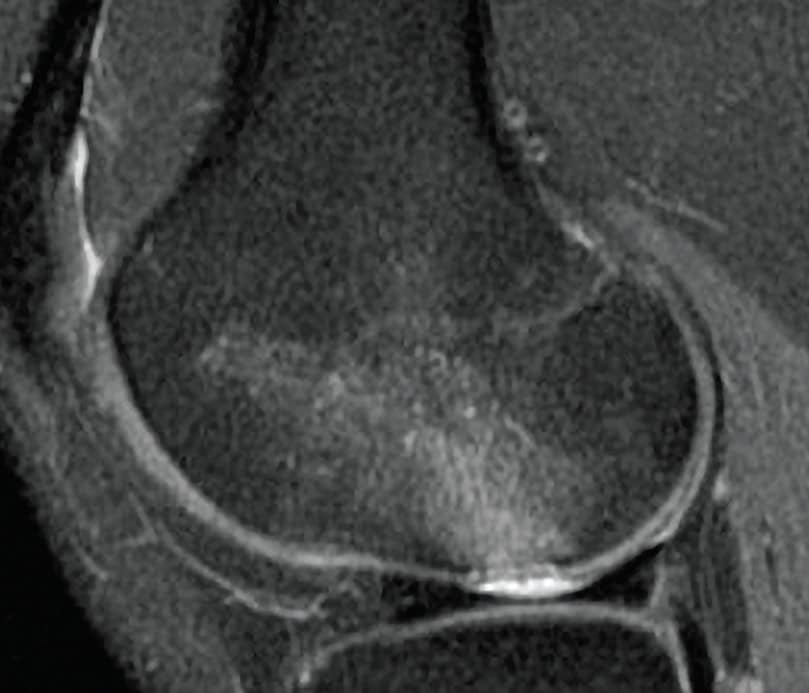

6 Months Post-Op MRI